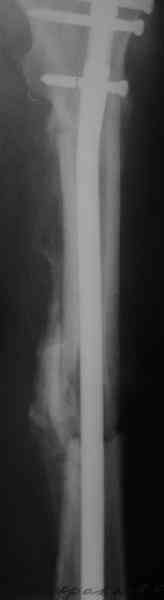

Судя по уровню перелома, винты в шейку избыточны, подойдет и диафизарный гвоздь. Все, что нужно, это тиски и труба. Загнуть сразу ниже отверстий градусов на 8-10, и вся недолга. Последние годы у нас это рутинная практика. Предызогнутые еще с завода гвозди неудобны тем, что они уже правый-левый.

Согласен, что закрытый реостеосинтез с рассверливанием и коррекцией оси - это то, что надо. Мы бы ввели в центральный отломок статических 2-3 винта, и один динамический винт в дистальном отломке.

Вот несколько. С тисками и трубой на днях сделаем.